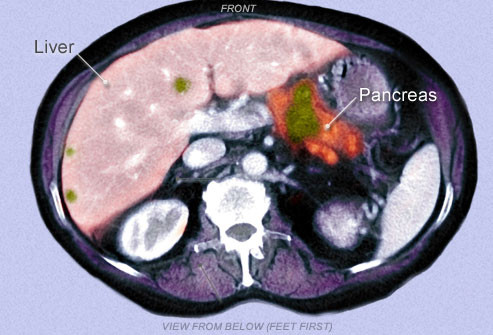

Tuyến tụy là bộ phận có hình tam giác thuôn dài nằm phía sau bụng, sát dạ dày có chức năng sản xuất các men (enzym) tiêu hóa giúp tiêu hóa thức ăn và sản xuất hormone bao gồm cả insulin tham gia quá trình chuyển hóa của cơ thể. Ung thư tuyến tụy xảy ra khi các tế bào (ung thư) phát triển, phân chia, và lây lan trong các mô của tuyến tụy.

Thách thức lớn nhất trong việc điều trị căn bệnh này là phát hiện sớm. Rất khó để xác định một người có mắc ung thư tụy hay không qua việc kiểm tra định kỳ sức khỏe. Để chẩn đoán ban đầu căn bệnh nguy hiểm này bác sĩ phải tiến hành các xét nghiệm và chẩn đoán hình ảnh thậm chí cần cả chụp cắt lớp hay sinh thiết mới xác định chính xác bệnh và giai đoạn của bệnh từ khối u.